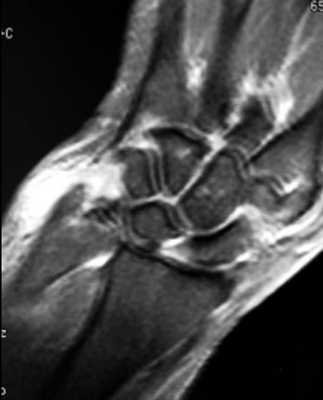

МРТ кисти. Корональная Т1-взвешенная МРТ. Нормальное изображение ладьевидно-полулунной связки. Обозначения: S - ладьевидная кость (scaphoid), L - полулунная кость (lunatum), T- трехгранная кость (triquetrum).

МРТ кисти. Корональная градиентная МРТ. Нормальное изображение полулунно-трехгранной связки. Обозначения: S - ладьевидная кость (scaphoid), L - полулунная кость (lunatum), T- трехгранная кость (triquetrum).